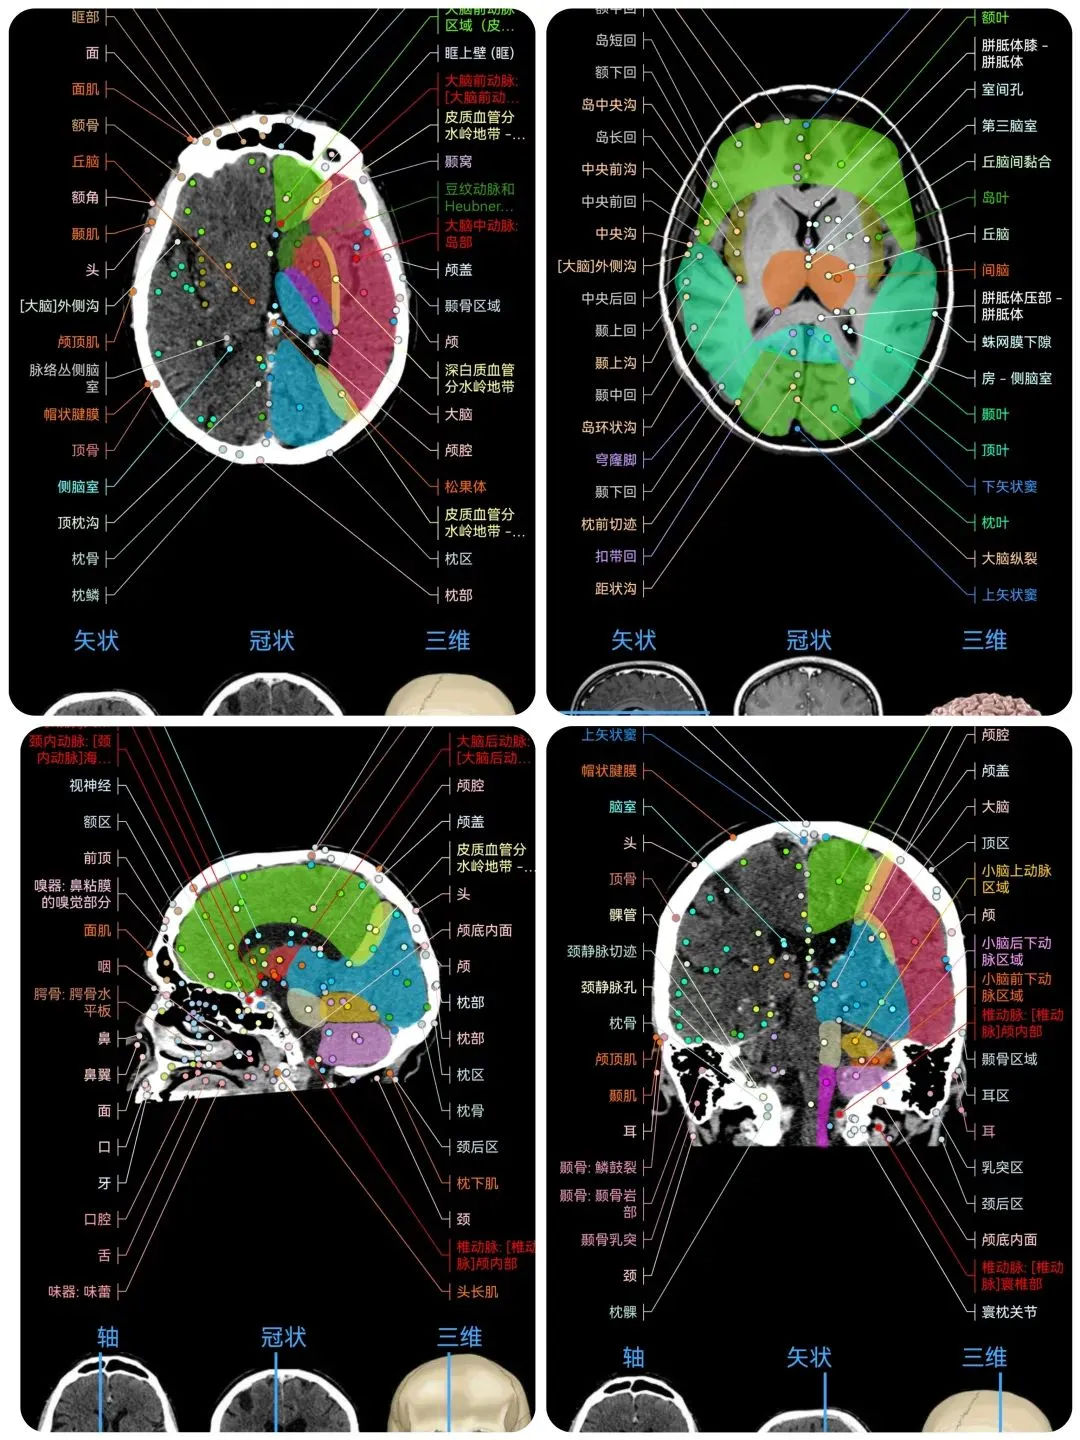

🌈这是国外引进的一款专业影像解剖学习软件。

覆盖了X光、CT、MRI、断层大体解剖、核医学、介入造影、医学插图等多个模块,覆盖全身各个系统的影像解剖(正常解剖结构,无病例),其中的解剖结构高达87万个,结构标注超精细,超高清图像,历时两年研发设计完成✅。